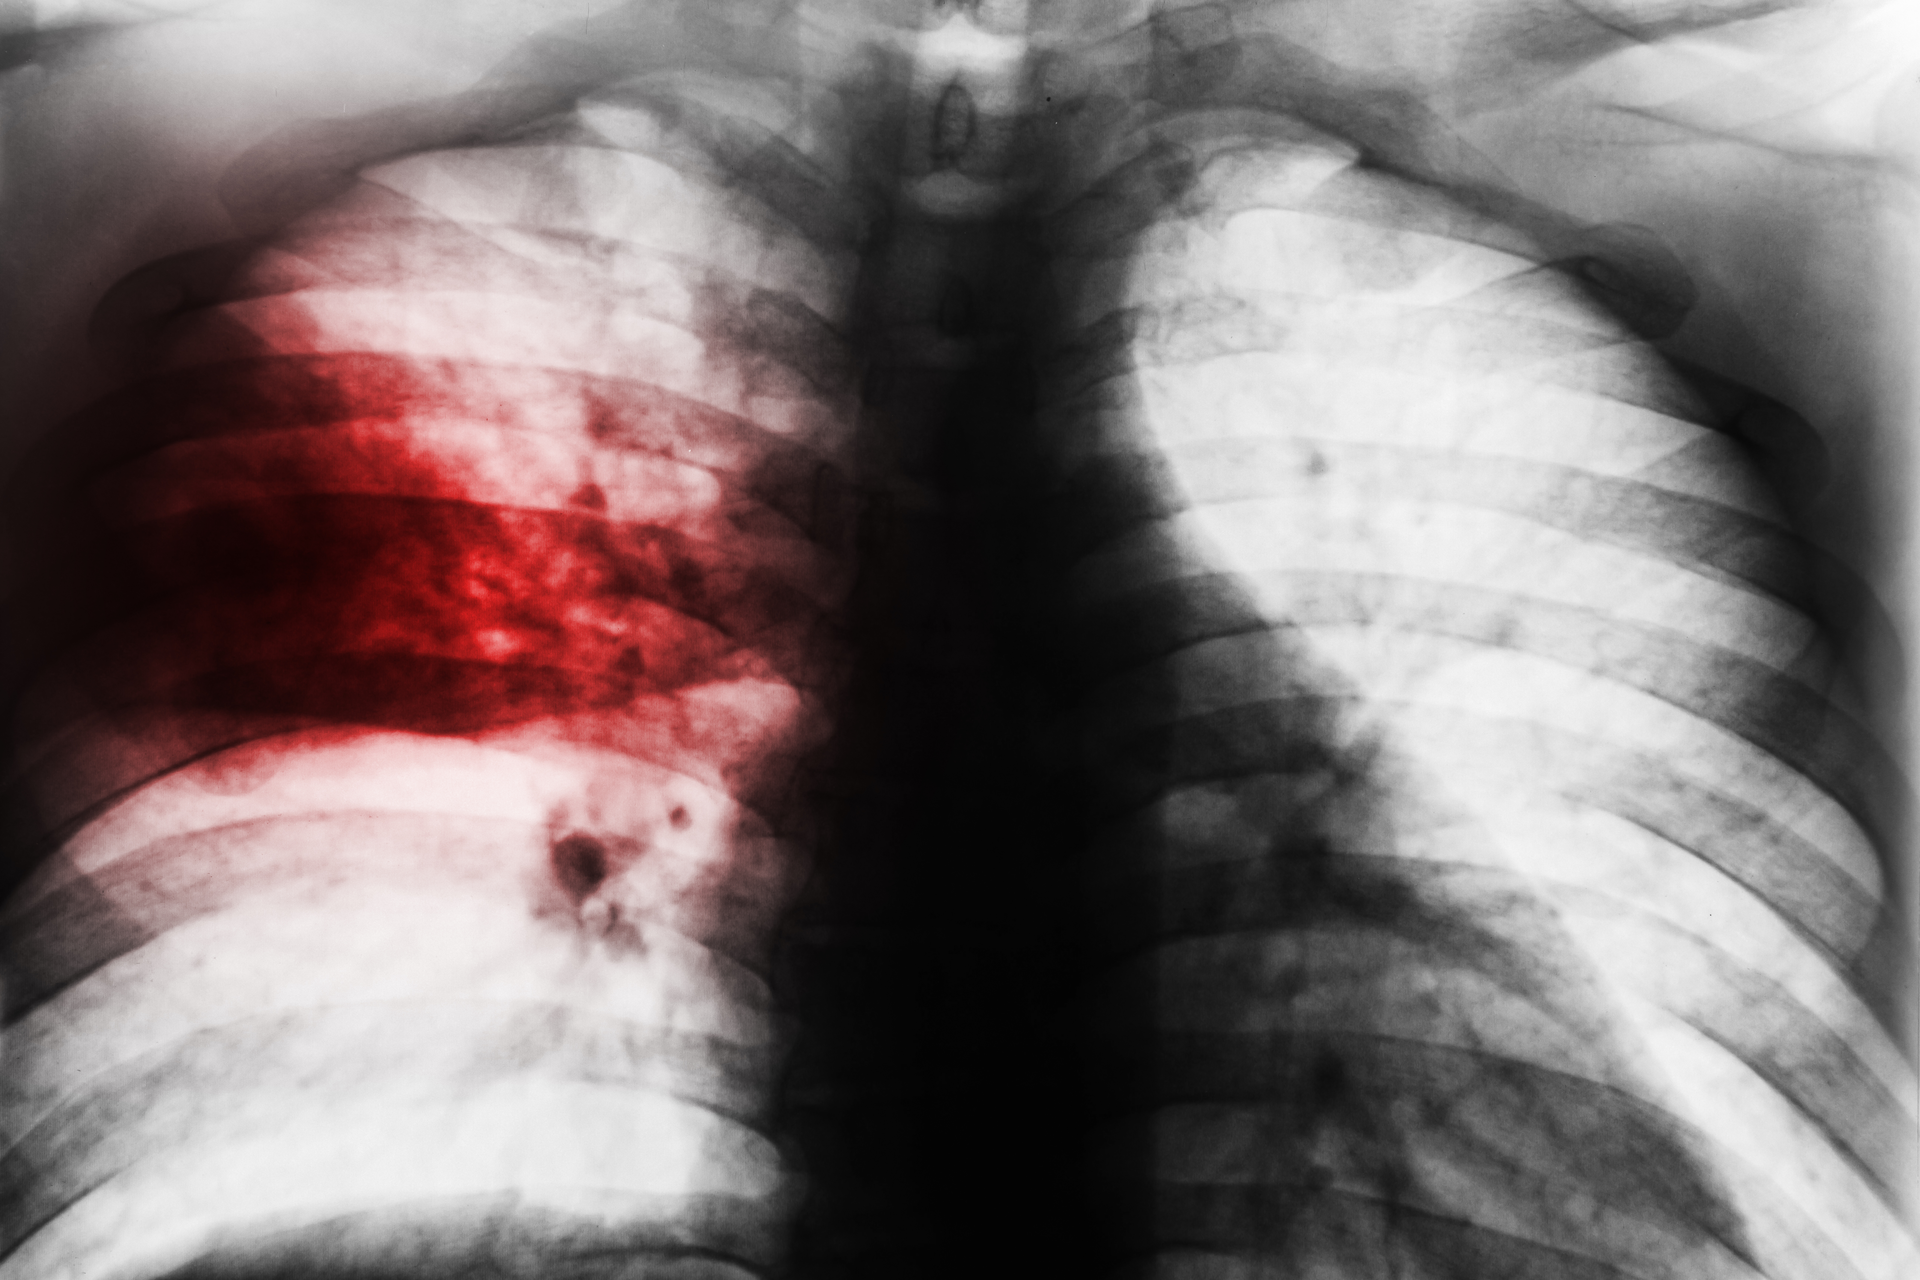

The U.S. Food and Drug Administration approved Xacduro (sulbactam for injection; durlobactam for injection), a new treatment for hospital-acquired bacterial pneumonia (HABP) and ventilator-associated bacterial pneumonia (VABP) caused by susceptible strains of bacteria called Acinetobacter baumannii-calcoaceticus complex, for patients 18 years of age and older.